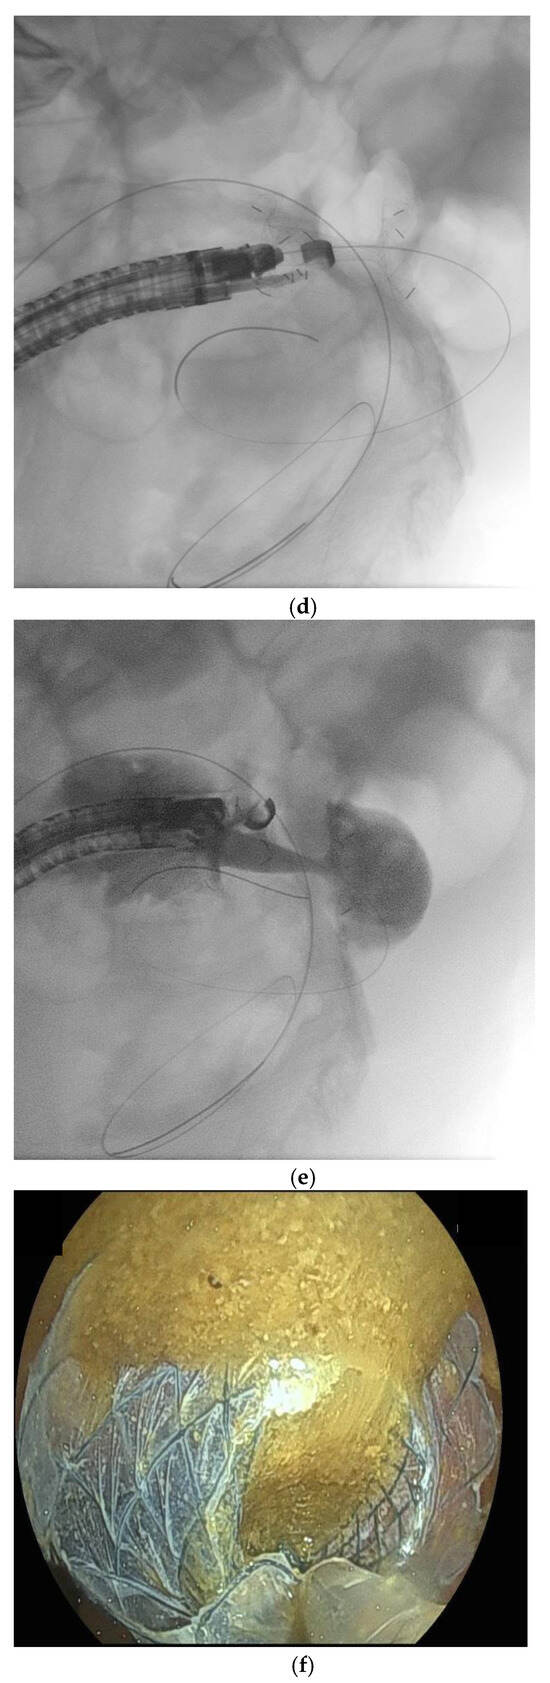

10. Endoscopic Ultrasound-Guided Entero-Colostomy with LAMS

- Jonica, E.R.; Mahadev, S.; Gilman, A.J.; Sharaiha, R.Z.; Baron, T.; Irani, S.S. EUS-guided enterocolostomy with lumen-apposing metal stent for palliation of malignant small-bowel obstruction (with video). Gastrointest. Endosc. 2023, 97, 927–933. [Google Scholar] [CrossRef]

- Mitsuhashi, S.; Kamal, F.; Shinn, B.J.; Chalikonda, D.; Tyberg, A.; Shahid, H.; Sarkar, A.; Kahaleh, M.; Chiang, A.; Kumar, A.; et al. Colonic-enteric lumen-apposing metal stents: A promising and safe alternative for endoscopic management of small-bowel obstruction. Gastrointest. Endosc. 2024, 99, 606–613. [Google Scholar] [CrossRef]

- Neri, B.; Stigliano, S.; Biasutto, D.; Citterio, N.; Lisotti, A.; Fusaroli, P.; Mangiavillano, B.; Donatelli, G.; Tonini, G.; Di Matteo, F.M. Endoscopic ultrasound-guided entero-colostomy with lumen-apposing metal stent as a rescue treatment for malignant intestinal occlusion: A multicenter study. Endoscopy 2025, 57, 77–82. [Google Scholar] [CrossRef]